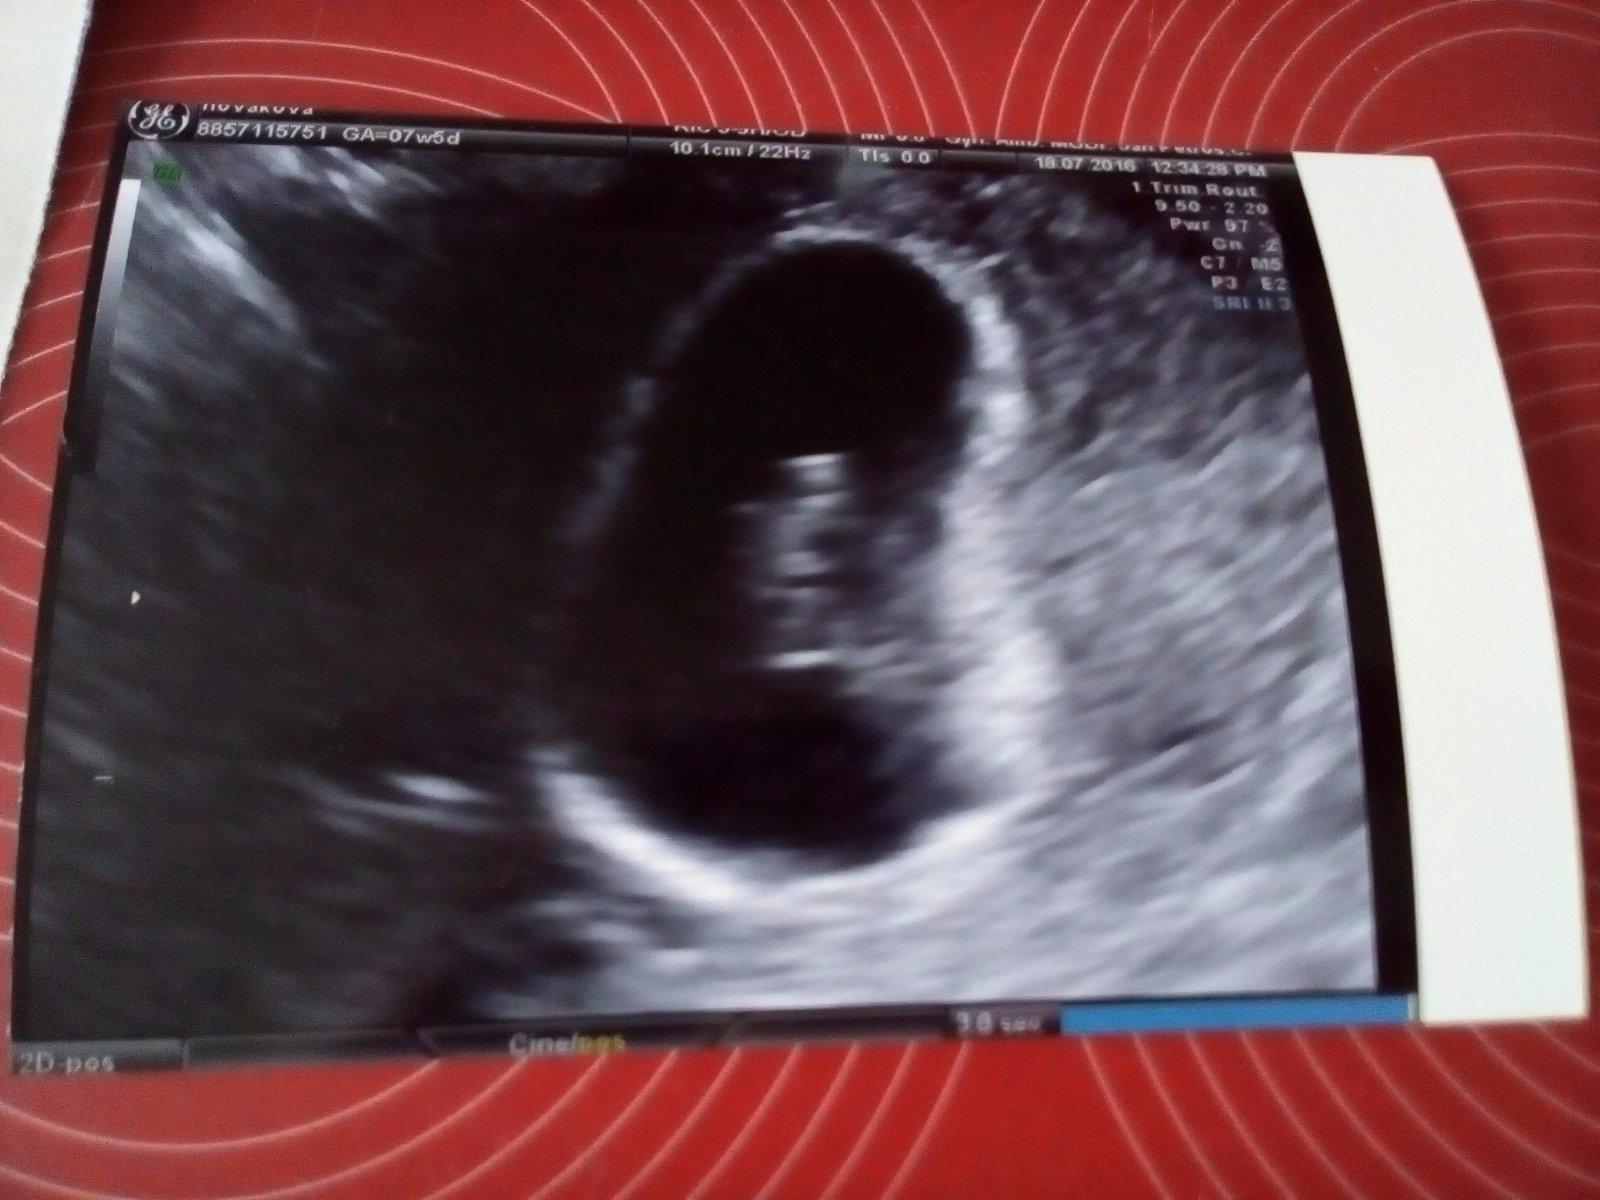

@petule407 ahoj 🙂 moc dekuji za optani. Na kontrole vse v poradku. Jsem v 7+5. A mimi je velke 13mm. Poustel mi srdicko, chtelo se mi uplne brecet :D tak mam hroznou radost! A co ty jak se ti dari?